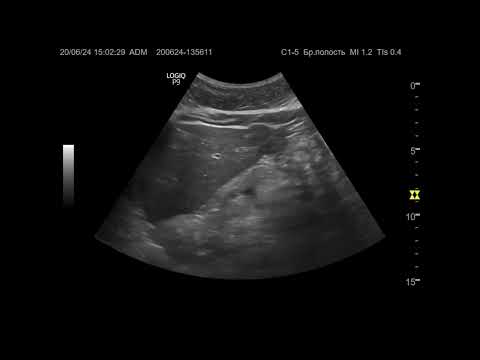

Ультразвуковая диагностика (УЗИ). Доктор Иогансен. Видеопримеры. Выпуск 86. Опухоль печени (4).